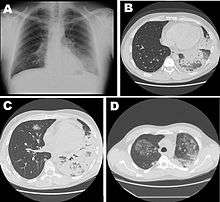

Laboratory tests may show that kidney functions, liver functions and electrolyte levels are abnormal, which may include low sodium in the blood. Chest X-rays often show pneumonia with consolidation in the bottom portion of both lungs. It is difficult to distinguish Legionnaires' disease from other types of pneumonia by symptoms or radiologic findings alone; other tests are required for definitive diagnosis.